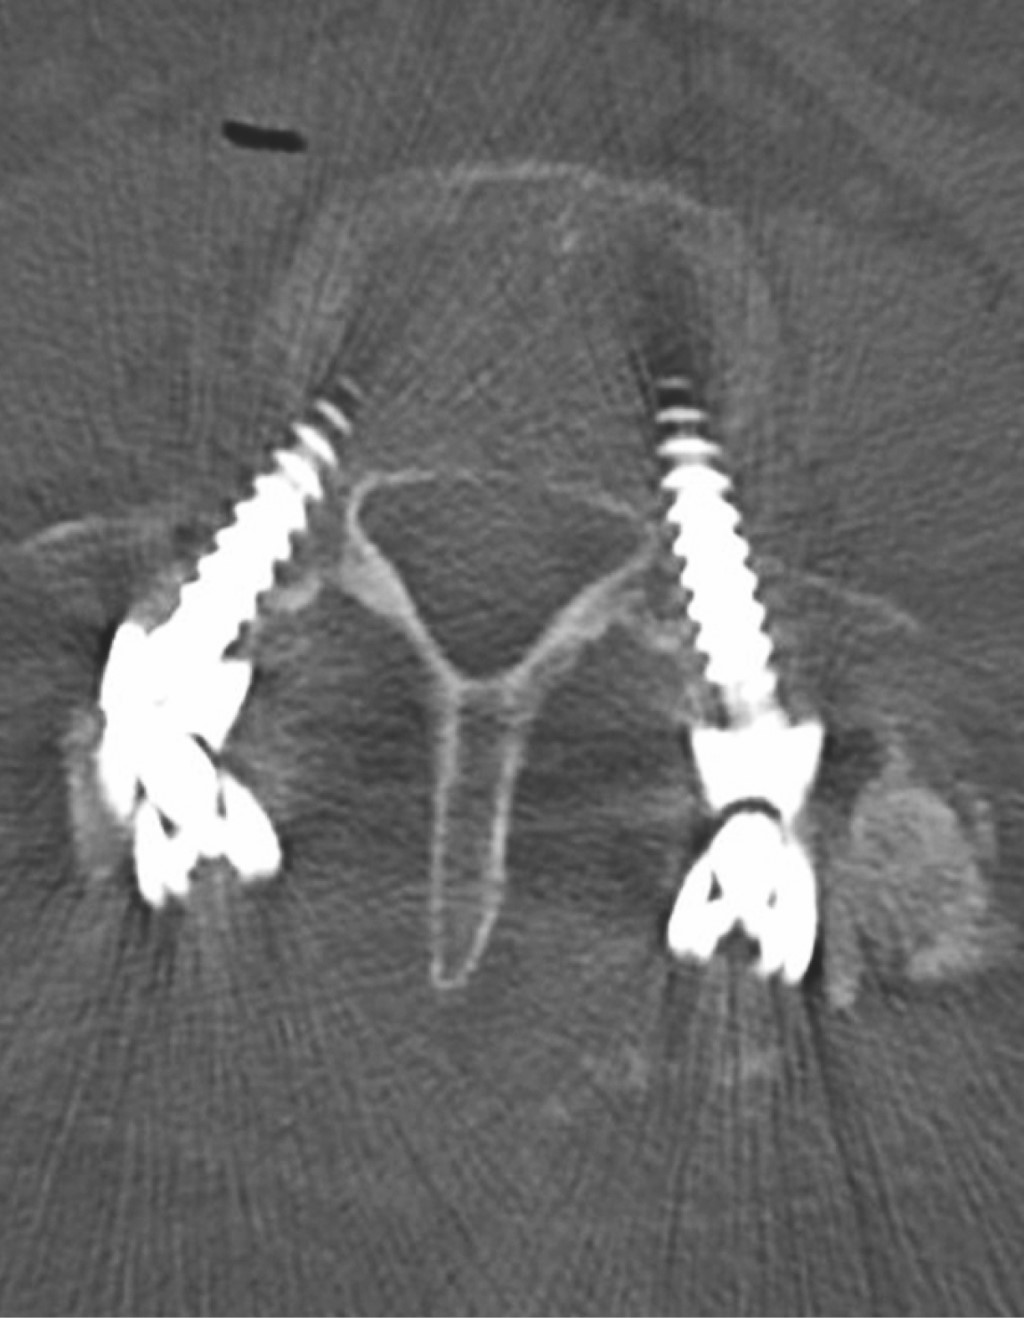

Ozone is a medical gas described since the 19th century; the ozone therapy has evolved to date in terms of its applications and its usefulness in various diseases due to its action at the molecular level and in dissimilar diseases associated with painful processes of inflammatory origin such as present in herniated discs of the spine, although the benefits of its application are currently in controversy, as well as the various complications that may occur after its application. Pneumocephalus is a complication that occurs in the background of a head injury or neurosurgery. Ozone infiltrations are used for the treatment of disc prolapse to reduce clinical symptoms. The anti-inflammatory effect of ozone is supported by its ability to oxidize compounds that contain double bonds such as arachidonic acid and prostaglandins, which are active substances with high concentrations in the inflammatory process. The appearance of pneumoencephalus and arachnoiditis chemical after epidural injection and also with ozone infiltrations is a rare complication but it has been described in recent years as a devastating post-application complication. Arachnoiditis can present as sensory and motor deficits, paresthesias, transient radicular neurological syndrome (TRNS), cauda equina syndrome, and conus medullaris. In relation to arachnoiditis, cases as severe as cauda equina syndrome after spinal anaesthesia, and more benign such as TSNR have been described, characterized by low back pain that radiates to the lower extremities, and not associated with motor deficits. neither sensitive, nor sphincter incontinence, which appears in the first 24 hours, which can last several days, and which resolves without neurological sequelae. Understanding the pathophysiology is important to assess and diagnose this type of neurological complications, especially in patients with disc disease who have undergone this type of treatment. The purpose of this report is to present the case of a patient with disc disease with the presence of radiculopathy who underwent infiltration by ozone therapy, who immediately presented complications such as pneumoencephalus and chemical arachnoiditis that led her to remain hospitalized in intensive care and present cauda equina syndrome.REFERENCES